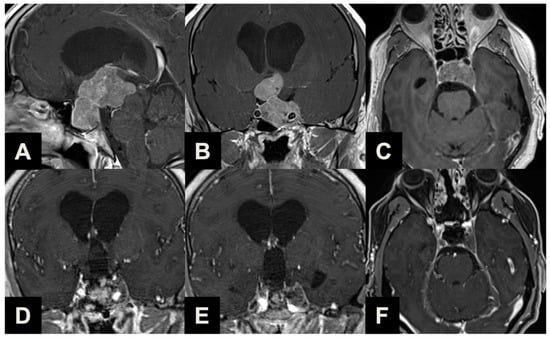

| Type 1 | Ectopic peduncular or supradiaphragmatic peri-infundibular PAs, including ectopic microadenomas of the pituitary stalk or purely supradiaphragmatic macroadenomas (mostly remnant or recurrence after previous partial surgeries). These tumors are not suitable for an EEA because they have no sellar infradiaphragmatic component. |

| Type 2 | PAs with sub-frontal extension, including macroadenomas with a supra- or infradiaphragmatic sub-frontal extension. These tumors are not fully resectable with an EEA because of their sub-frontal component, which extends anteriorly with an unfavorable angle and direction for the trans-sphenoidal approach. |

| Type 3 | PAs presenting with a major extrasellar component, including macroadenomas with suprasellar supradiaphragmatic component exceeding the sellar volume (i.e., air balloon PAs) unlikely to be delivered through the sella with an EEA, and macroadenomas with both a large intrasellar infradiaphragmatic part and a large suprasellar supradiaphragmatic portion connected through a narrow isthmus (i.e., snowman PAs), which impairs their resection through an EEA. |